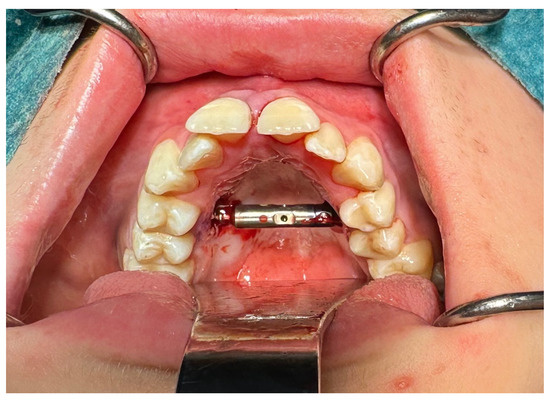

| Perforation of the maxillary alveolar process caused by the distractor—1 case | Maxillary incisor necrosis—2 cases |